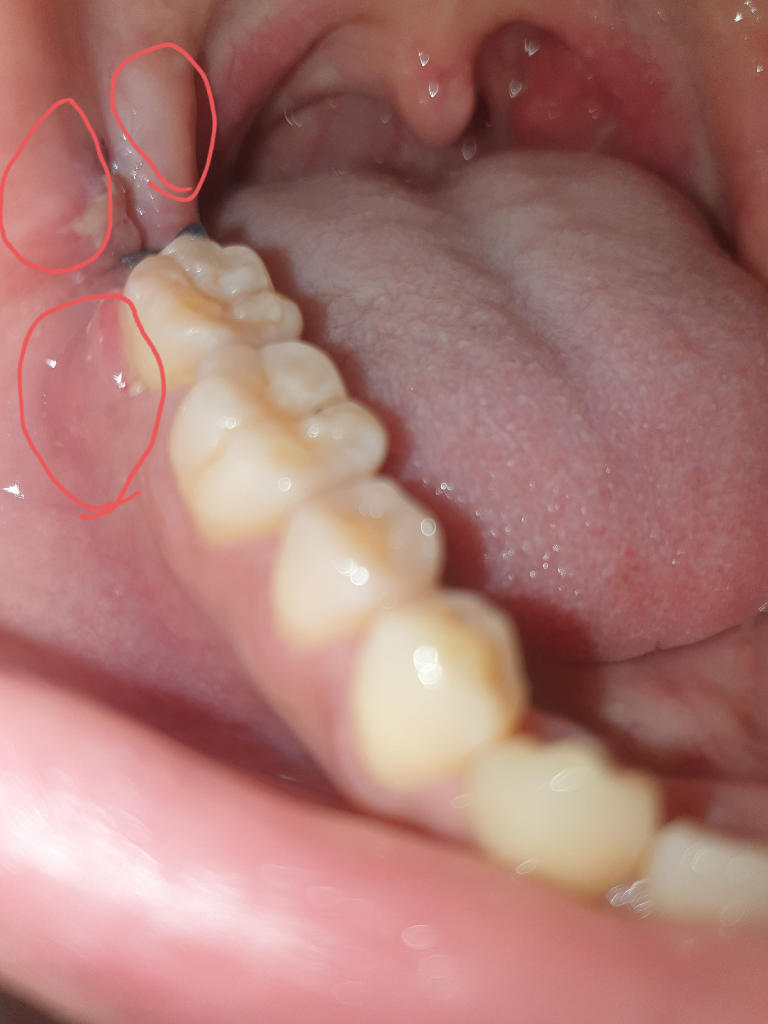

매복사랑니 발치 5일차 통증이 이상해요. 미치겠어요 도와주세요 의사님들 사진 첨부합니다

2. 표시한곳이 피멍든것처럼 누르거나 힘이들어가면 찢어지듯이 아프고 압통이 생겨요 ㅜㅜ

• 1번 째 사진

2. 누르거나 자극을 하지 않는 것이 좋으며 현재 사진으로 보아서는 정상적인 회복 과정입니다.